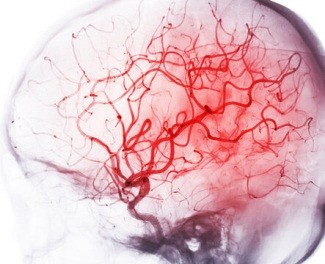

Следующим фактором риска после БА статистически является нарушение мозгового кровообращения, то есть, сосудистая природа развития деменции. В отличие от болезни Альцгеймера, которая распознается преимущественно у пожилых людей, острые нарушения мозгового кровообращения (ОНМК) не всегда зависят от возраста. В зависимости от образа жизни, наследственности такие эпизоды не исключены и у молодых пациентов. Клинически значимыми факторами риска в этом случае выступают атеросклероз сосудов, наличие тромбов, болезни сердца (ИБС), изменения в шейном отделе позвоночника, и прямо связаны с деменцией цереброваскулярной природы.